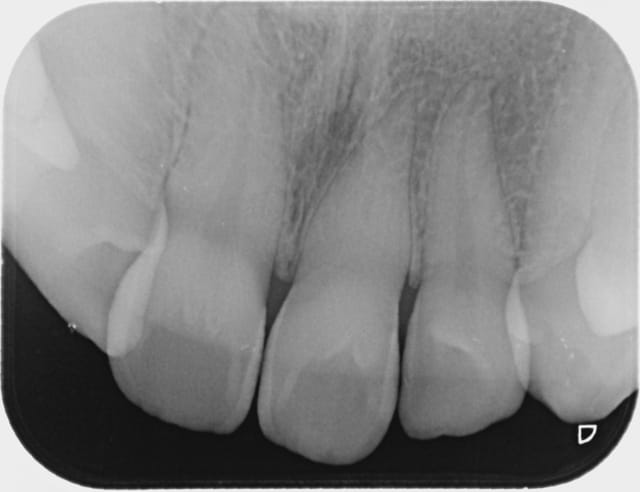

Merci du cas , ça m'intéresse car j' ai vu plusieurs patientes dans ce cas avec canal totalement calcifié invisible à la radio mais je n' aurais jamais osé faire un éclaircissement interne car les dents sont vivantes même si leur réponse aux stimuli est atténuée. Combien as- tu de recul? Pas de nécrose par la suite? J' avais tenté un éclaircissement externe mais cela a très mal marché malgré trois séances. Dans deux cas je pense que la calcification est dûe à un trauma occlusal, dans le troisième que j'ai pu voir il s' agit peut-être de forces ortho excessives. Les trois cas que j' ai en tête, car il y a un moment que je ne les ai pas vues, concernaient exclusivement des femmes, mais peut être qu' elles ont plus tendance à consulter que les hommes pour ce motif, par coquetterie.

Et si la cause de la calcification était la nécrose par rupture du paquet vasculo-nerveux ? (hypothèse très probable, micro-traumatismes répétés, habitudes nocives).

J'ai un cas où 11 et 12 ont subi un trauma dans l'enfance avec lésion englobant les 2 apex. 11 a été fracturée et a donné une lésion apicale tandis que 12 a seulement été déplacée mais a subi une calcification du canal, invisible à la radio. Il serait intéressant de savoir si une cicatrisation est possible en ayant uniquement obturé 11. Je posterai la radio demain.